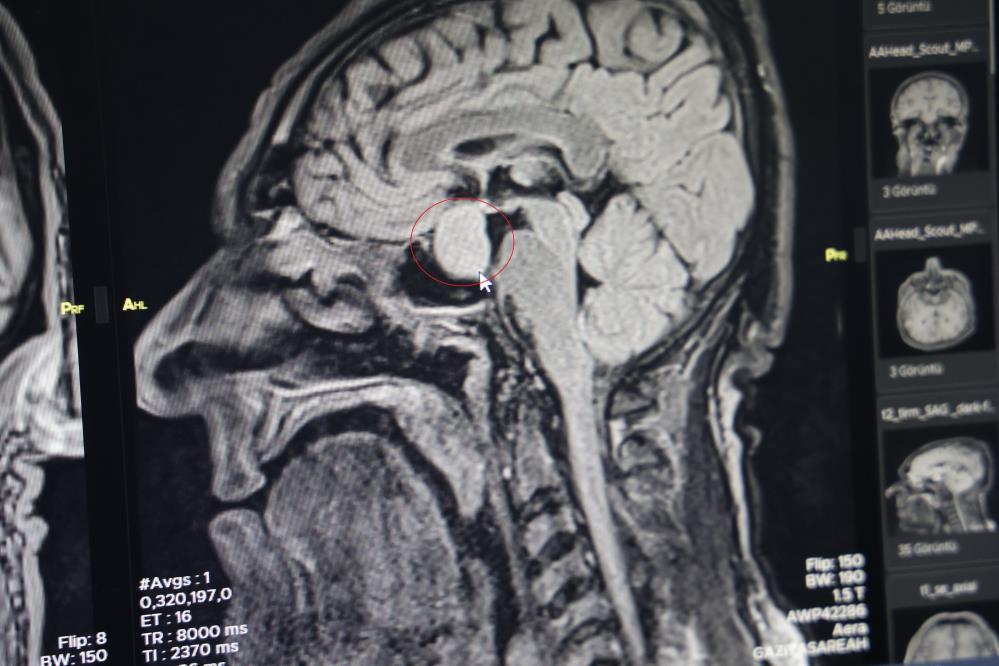

Hastanın dış merkezlerde çekilen MR’larında hipofiz bölgesinde bir iyi huylu tümör tespit edilmesi ve tavsiye üzerine kliniğine başvurduğunu belirten Dr. Çetin, hastanın yatışını yapıp ileri tetkiklerini yaptıklarını kaydetti.

Dr. Çetin, hormonlarına baktıklarında hastanın büyüme hormonları yüksek olduğunu söyleyerek, "Hastayı yapacağımız ameliyat ile ilgili bilgilendirdik. Hastanemizde ilk defa burundan kapalı yöntemle girilerek hipofiz tümörüne müdahale ettik. Allah’a şükür sağ salim bir şekilde, her hangi bir komplikasyon gelişmeden tümörü aldık. İki gün sonra da hastamızı taburcu ettik. Operasyonumuz 2-2,5 saat sürdü. Herhangi bir riskle karşılaşmadık. Hastamızın genel durumu şu an gayet iyi. Kan tetkiklerinde ve hormon düzeyinin de düştüğünü büyük bir memnuniyetle gözlemledik" dedi.

"Kendi açımız ve hastanemiz açısından güzel oldu, gururlandık" diyen Dr. Çetin, "Hipofiz bezinde yetmezlik ve görme sinirlerinde baskı yaptığı zaman görme kaybına neden olabilmektedir. Bu hastamızda ameliyat öncesi görme kaybı bir miktar vardı. Büyüme hormonu oldukça yüksekti. Tümörü boşalttığımız için hormon düzeyi yarıya düştü. 2-3 hafta sonra kontrole gelecek bir daha ölçme imkanı bulacağız. Bu hastalar genelde şimdiye kadar büyükşehirlere gitmekteydiler. Bundan sonra bu tür ameliyatları gerçekleştirme imkanı bulacağız" şeklinde konuştu. (İHA)